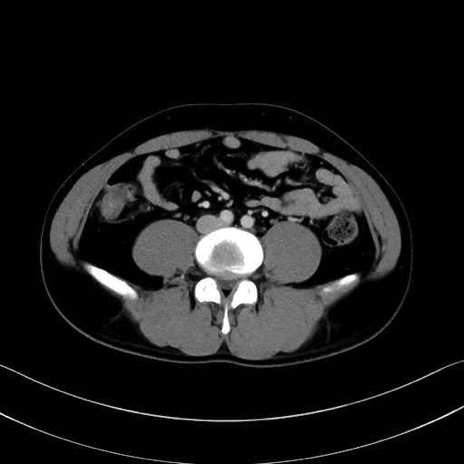

腰方形筋(quadratus lumborum muscle)のCT画像の解剖

症例

1. 体幹部(腹部・背部・後腹壁)の筋肉

腰方形筋 (Quadratus lumborum)

広背筋 (Latissimus dorsi)

脊柱起立筋 (Erector spinae)

多裂筋 (Multifidus)